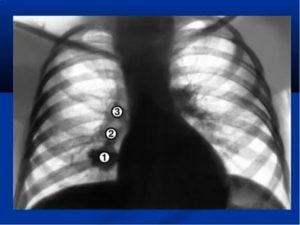

Воспалительный процесс лимфоузлов лёгких можно разделить на несколько стадий. От заражения бактериями, до полноценного заболевания. Классифицируются воспаления по фазам:

- 1 фаза – это поражение внутригрудных узлов микроорганизмами;

- 2 фаза – появление паталогии в корнях лёгких без образования фиброза;

- 3 фаза – поражение сердечно-лёгочной системы, с образованием фиброзов очагового и диффузного характера.

Увеличенные лимфоузлы легких на рентгене видны, когда болезнь переходит во вторую фазу, сначала «под удар» попадают бронхиальные, а на третьей стадии средостенные, бронхолегочные и надключичные узлы.